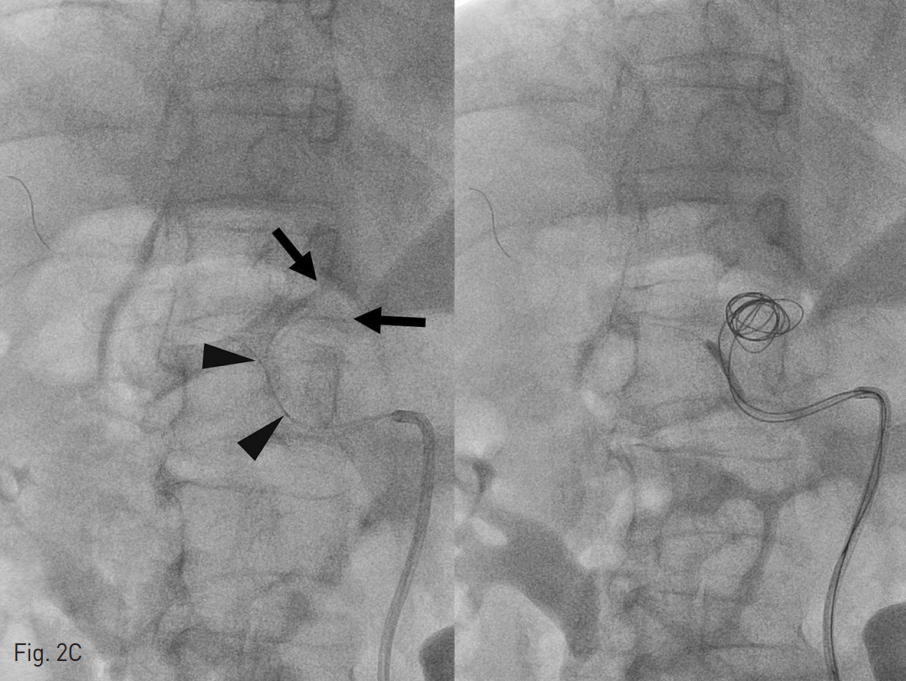

우선, 동맥류의 정확한 모양을 확인하기 위해서, 우측총대퇴동맥에 5 Fr sheath를 retrograde insertion 한 후 RH catheter를 이용해서 common hepatic artery의 DSA (Fig. 2A)와 cone-beam CT(Fig. 2B)를 시행함. Properhepatic artery의 직경은 약 2.8mm, 길이는 1.8cm, aneurysm의 neck은 1.3cm 정도임. 동맥류의 coil embolization시행으로 hepatic arterial supply에 문제가 발생하면 간수치의 상승으로 환자의 수술 스케줄이 지연될 것이라 생각함. 이에 proper hepatic artery를 보존하기 위해서 balloon-assisted coil embolization을 계획함. 우측총대퇴동맥 sheath를 8 Fr sheath로 교체한 후, 8 Fr guiding catheter를 common hepatic artery까지 진입시킴. Y-connector 3개를 연결시켰고 heparin이 섞인 N/S로 guiding catheter 내부가 계속 flushing되도록 함. Microcatheter와 guide wire를 이용하여 proper hepatic artery aneurysm을 지나 우측 간동맥 peripheral portion까지 도달 한 후, 길이 300cm의 0.014 wire로 교체하고 micro balloon을 삽입하여 aneurysm neck에 위치시킴. Balloon에 의한 proper hepatic artery손상을 최소화하기 위해, proper hepatic artery의 직경보다 작은 2.5mm x 2cm balloon을 사용함. 이후 동맥류 내부에 골고루 coiling

이 되도록 2.5 Fr Renegade (straight type)과 2.5Fr Renegade STS (angled ty pe)를 동시에 insertion하여 두 개의 catheter tip이 각각 동맥류 내부의 다른 위치에 위치하도록 navigation시킴 (Fig 2C). Balloon을 inflation시킨 후, 2개의 microcatheter를 통하여 interlock coils을 사용하여 embolization 시작함. Aneurysm neck으로 coil이 빠져 나오지 않도록 interlock coils을 사용하여 아주 주의 깊게 coil packing을 진행함. 최종적으로 직경 14mm ~3mm 크기의 interlock coils을 모두 24개를 사용하여 동맥류의 내부를 완전히 채움. Follow up celiac angiography에서 동맥류은 coiling packing되어 flow는 전혀 보이지 않았고, proper hepatic artery 의 flow는 유지되어 liver쪽으로 perfusion이 이루어지고 있는 것을 볼 수 있음 (Fig. 2E). Proper hepatic artery가 약간 가늘어 보이나, balloon inflation에 의한 vasospasm의 영향을 고려했을 때, 시간이 지나면 좀 더 좋아질 것으로 생각하고 시술 종료함.

Fig. 2. Balloon-assisted coil embolization

C. Two microcatheters (arrows) were inserted into the aneurysm. 2.5mm x 2cm balloon (arrowheads) was located at the aneurysm neck. After inflating balloon catheter, coiling was started through microcatheters.